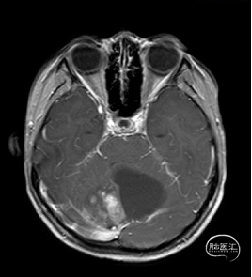

现病史:患者18个月前无明显诱因出现间断头痛,休息后可缓解,开始未予重视,未行特殊治疗。1周前患者无明显诱因出现恶心、呕吐,就诊于当地医院,行颅脑MRI提示:小脑囊实性占位性病变,首先考虑毛细胞星型细胞瘤。现患者为求进一步治疗就诊于我院,门诊以“脑肿瘤”收入院。患者自发病以来神志清,精神可,饮食睡眠正常,二便如常,体重未见明显下降。

术前MRI